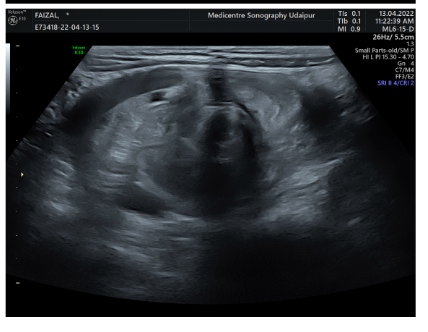

2 YEAR MALE CHILD PRESENTED WITH ACUTE VOMITING FROM 4 DAYS DIAGNOSED WITH PROXIMAL INTESTINAL MALROTATION WITH REVERSAL OF SMA-SMV AXIS ON ROUTINE USG OF ABDOMEN CONFRIMED ON COLOUR DOPPLER